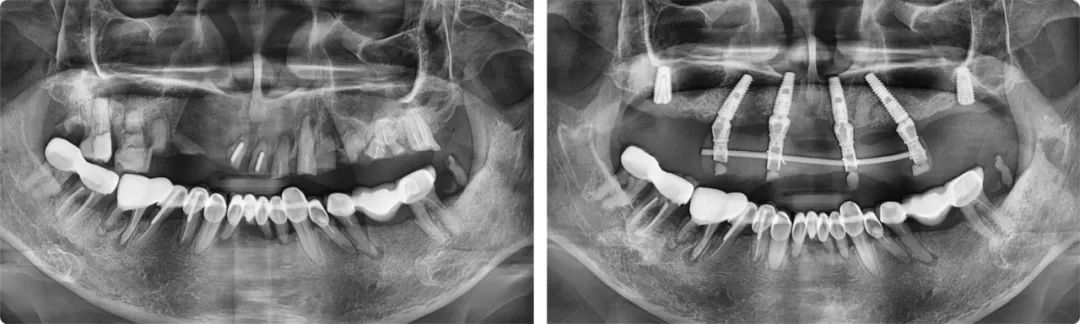

患者術(shù)前術(shù)后全景片